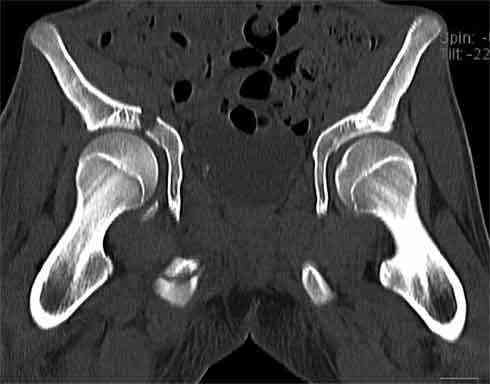

Не смог разглядеть на представленных картинках частичное повреждение левого КП, повреждение Денис1-2 справа? 3Д реконструкции в инлет и боковой проекциях убедительно не демонстрируют типа повреждения задних отделов тазового кольца(справа боковая масса скомпремирована), Наверное, у тебя есть возможность оценить тип перелома крестца по прямой проекции 3Д.

Думаю, что КТ заднего отдела показала бы ясно тип повреждения .

По вертлуге- смог разглядеть только изолированный перелом передней колонны.

Насколько я понял из твоего письма, обращенного к анонимному vit, ты не видишь показаний к реконструкции перелома. Я бы взялся за реконструкцию(илео-ингвинальный доступ), хоть прошел и месяц после травмы: боковая 3Д показывает смещение нагрузочной зоны впадины, что однозначно будет способствовать разрушению хряща головки и впадины( особенно у 16 летнего пациента с ожидаемым высоким уровнем активности) + изменение геометрии впадины за счет неустраненного смещения фрагментов колонны (КТ, 3Д данные).

На мой взгляд, без реконструкции этот сустав обречен (концепция вторичной конгруэтности в данных условиях работать не будет), реконструкция дает шанс на восстановление функции сустава.

В данном случае 3D и корональные срезы КТ менее информативны, чем поперечные. Согласен с левосторенним минимальным повреждением КПС, но не смог уловить перелом крестца.

На 3D по линии перелома ацетабулум возможно сверху в подздошной кости уже есть сращение? или состояние перелома у молодых, после неполного (при пластической деформации) перелома.

По представленным материалам, мне кажется, перелом был передней колонны ацетабулум с минимальным вовлечением нагрузочной поверхности сустава, левосторенний повреждение КПС и лонных костей.

При свежем случае показана фиксация передней колонны к задней (снимки), компрессирующим винтом минимальным перкутанным методом по супраацетабулярной линии и в зависимости от состояния КПС.